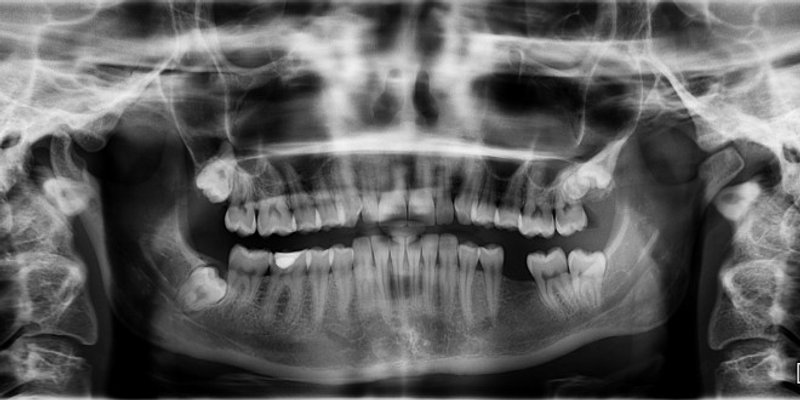

Dobro je paziti na zdravlje usta i pratiti sve promjene - jer bi one mogle pokazivati da postoje upale ili negativne promjene s kojima se vaše tijelo bori. Redoviti pregledi kod zubara pomoći će jer se onda mogu na vrijeme uočiti stvari koje biste bez pregleda mogli propustiti.

3. Osteoporoza i gubitak zuba

Ako smatrate da vam je olabavio korijen jednog ili više zuba, mogli biste patiti od osteoporoze.

Kost oko vaših zuba pruža osnovu koja ih podržava. Iako je to kod kuće teže otkriti, stomatolozi i higijeničari moći će vidjeti sustavnu promjenu gustoće kostiju zbog osteoporoze.

Zubi koji se tijekom pregleda više od prosjeka klimaju mogli bi biti rani trag ovom progresivnom stanju. U tim slučajevima često se preporučuje ispitivanje gustoće kostiju kod liječnika.